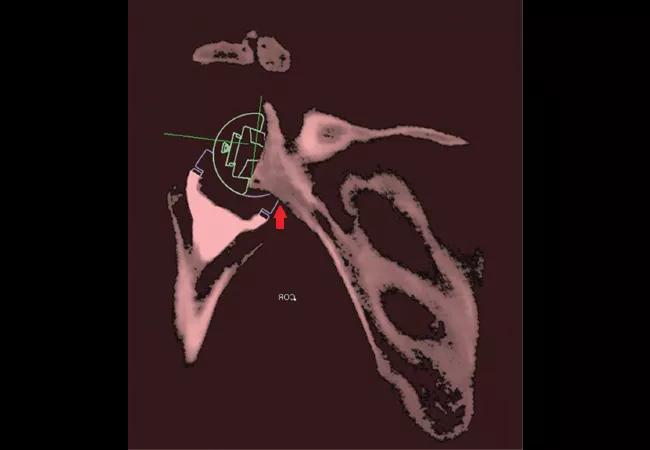

Thirty patients with preoperative CT scans who underwent rTSA were evaluated at minimum two-year follow-up with VMA, postoperative 3-D CT with metal artifact reduction techniques and standard radiographs. Reflective markers were placed on each patient’s skin at specific bony prominences on the forearm, arm, scapula and thorax to perform VMA of patients’ shoulder ROM during active abduction/ adduction and internal rotation/external rotation with the arm at the side. Glenohumeral ROM was then determined for each patient from VMA. This information was then combined with postoperative implant location from 3-D CT in custom 3-D CT kinematic simulation software to determine areas of bony impingement between the humeral implant and scapula (Figure 1).

Figure 1 Digital templates for the humeral and glenoid components were aligned with actual component positions on postoperative CT. Postoperative glenoid implant position was then registered to the preoperative CT using an image overlay technique available in the 3-D imaging software, such that the position and orientation of the glenoid component digital template on the postoperative scapula was transferred to the preoperative scapula, as shown in Figure 1. The postoperative humerus and the position and orientation of the humeral component digital template were mated to the preoperative scapula with postoperative glenoid component digital template as part of the overlay technique. During 3-D CT kinematic simulation of patients’ glenohumeral ROM, an automated detection method within the custom-designed 3-D imaging software detects impingement between the humeral component and the scapular neck, shown by the red arrow in the figure.